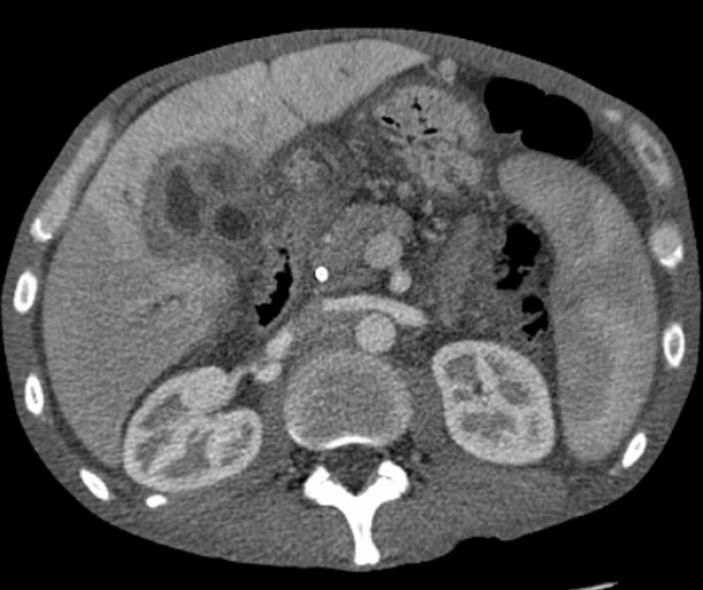

胆管細胞癌のCT画像